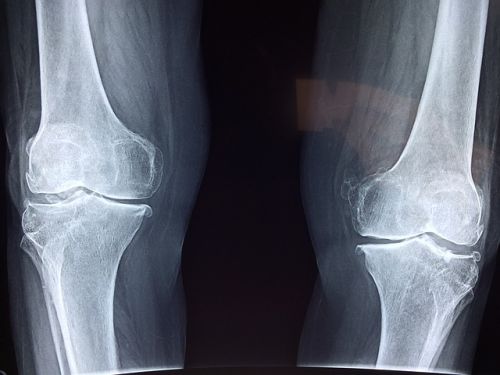

영상 검사

엑스레이와 초음파 검사도 진단에 유용합니다. 엑스레이는 관절의 손상 정도를 파악하는 데 도움을 주며, 초음파 검사는 요산 결정을 시각적으로 확인할 수 있도록 도와줍니다. 이러한 도구들을 통해 관절의 상태나 구조적인 이상을 확인할 수 있습니다.